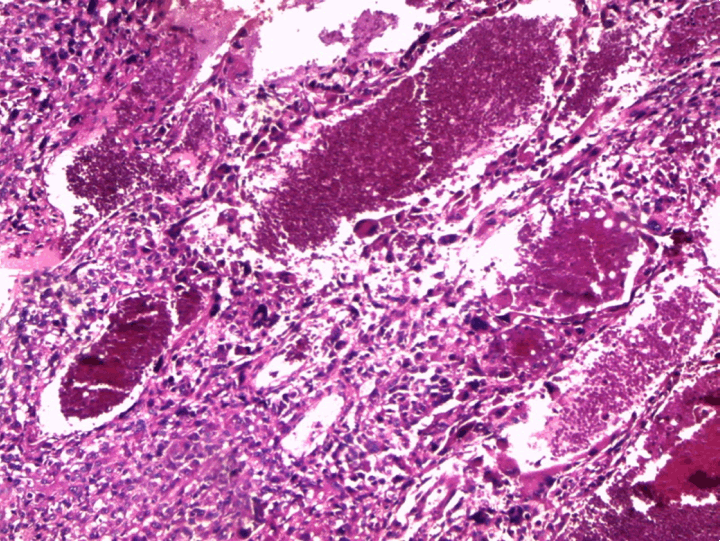

At the pathology laboratory, we received a piece of the left lower limb amputation. (Figure 2) We opened it. Gross examination of the resected distal femur revealed a 22x5 cm intramedullary multicystic hemorrhagic destructive tumor with cortical destruction and extension into the adjacent anterior and posterior soft tissues. The latter component of the mass was larger than the intraosseous tumor. (Figure 3) The articular surface was not involved. We cut the femur in its longest axis with electric saw. (Figure 4) Fixation in 10% neutral buffered formalin for 48 hours and decalcification of bone with nitric acid were performed. Slice of bone section was included in full. Many specimens from soft tissues and the surgical margins were also taken. Microscopic view of histological specimens of tumor stained with hematoxylin andeosin showed prominent blood filled cysts with malignant stroma in septa separating cysts. (Figure 5) (Figure 6) It contained atypical tumor cells oval or round of variable size with osteoblast-like multinucleated giant cells and a variable amount of immature osteoid. (Figure 7) (Figure 8) (Figure 9) (Figure 10) (Figure 11) (Figure 12) Numerous mitotic figures were noted (Figure 13). The tumor was located at 6 cm from the bone limit and 2 cm at the edge of the soft tissues. The resection margins were negative. The marrow, scooped and submitted separately, was negative.

Figure 9: (A, B) High magnification showing nuclear pleomorphism of sarcomatous septal cells and tumor giant cells (H&E stain, x400).

Figure 10: Tumor osteoid in septum bordering blood-filled space. Higher magnification showing irregular, finely divided (lace-like) strands of osteoid (H&E stain, x400).